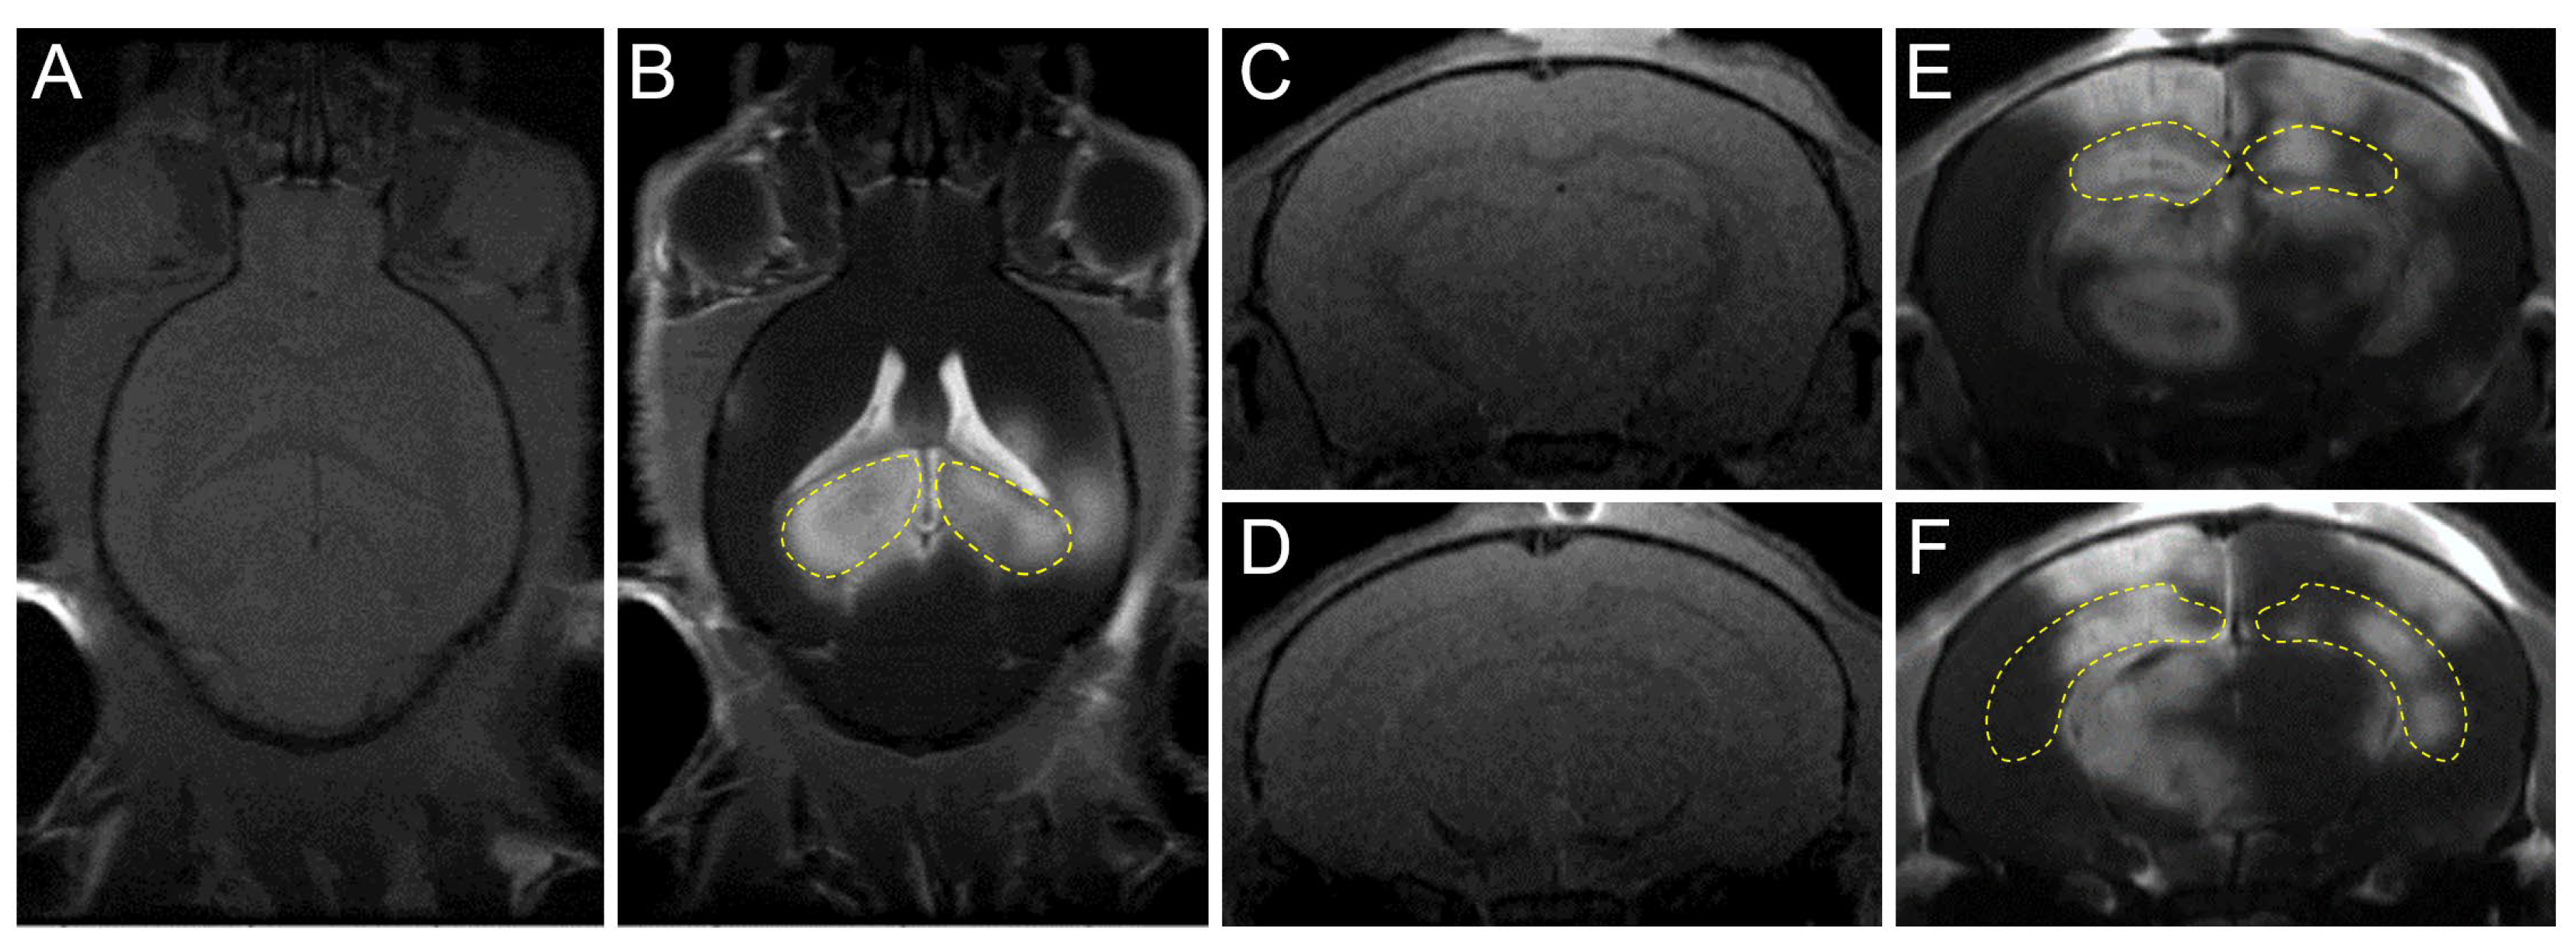

- Kong, C.; Yang, E.-J.; Shin, J.; Park, J.; Kim, S.-H.; Park, S.-W.; Chang, W.S.; Lee, C.-H.; Kim, H.; Kim, H.-S. Enhanced delivery of a low dose of aducanumab via fus in 5× fad mice, an ad model. Transl. Neurodegener. 2022, 11, 57. [Google Scholar] [CrossRef] [PubMed]

| Kong (2022) [42] | 5×FAD mice | CF:0.5 MHz PRF:1 Hz TD:120 s AP:0.25 MPa | Hippocampi | Combined therapy of FUS and Aducanumab decreases amyloid deposits, increases neurogenesis, and attenuates cognitive function deficits. |